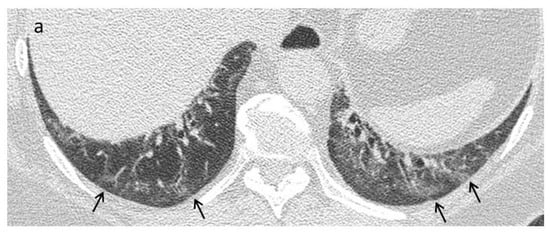

| Early stage | NSIP pattern:

|

| Late fibrotic stage | Fibrotic NSIP/UIP pattern: